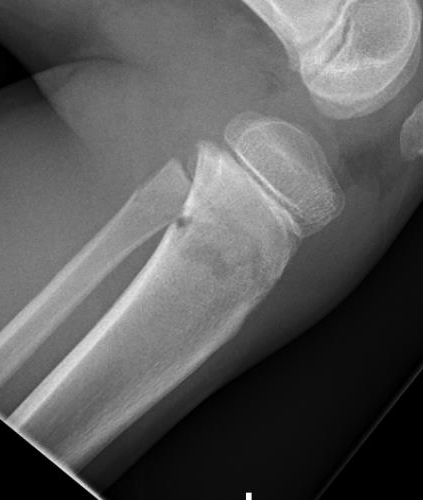

Manipulation and casting of malaligned Cozen fracture under anesthesia

Valgus malalignment